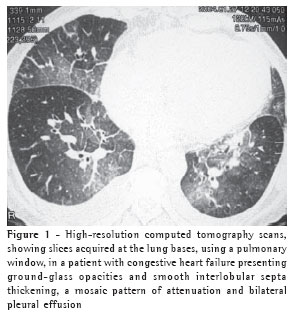

The thickening of the interlobular septa was bilateral in thirteen cases (Figures 1-4) and unilateral in two, also in the patients with fibrosing mediastinitis. In all cases, the thickening was of the smooth type.

Peribronchovascular interstitial thickening was observed in twelve cases (80%), being bilateral in ten (Figure 4) and unilateral in two (the cases of fibrosing mediastinitis).

Septal thickening was not found in isolation. In all patients presenting septal thickening, there were also ground-glass opacities, and the mosaic pattern of attenuation was observed in ten patients (67%). In another study,(9) interlobular septal thickening was also not observed as an isolated tomographic finding, although its presence was closely correlated with peribronchovascular interstitial thickening.